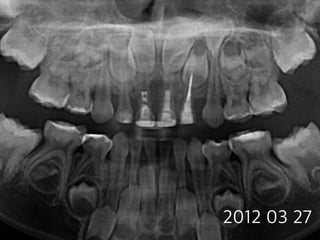

#54,#74,#84 pulpotomy

(8 female)

2012 03 27

2014 10 15

#74 2012 12 21

#84 2013 05 28

2014 07 17

#54

#74

#84

22m later

16m later

3m later